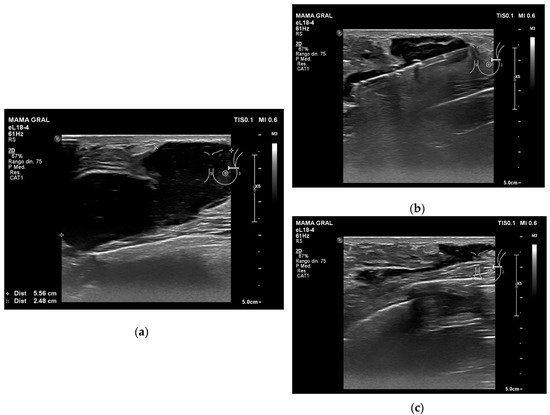

Figure 3. Example of VAB evacuation of a haematoma after VAB excision of a fibroadenoma: (a) the ultrasound image shows a hypoechoic-heterogeneous haematoma; (b) a vacuum-assisted biopsy needle was inserted into the haematoma cavity and we evacuated fluid until the collection disappeared; (c) residual fluid.

The US appearance of the 8 haematomas in this study was a mixture of hyperechoic-heterogeneous (n = 4) and hypoechoic-heterogeneous (n = 4). The mean time between VAB excision of the lesion and VAB evacuation of the haematoma was 10.1 ± 3.9 days (range: 10–14 days). The average duration of the VAB evacuation of the haematoma was 5.8 ± 1.3 min (range: 4–8 min). Only one patient had VAB evacuation of the haematoma 24 h after VAB excision of the lesion due to intense pain (VAS = 7), which managed to reduce the pain (VAS = 5). In this case, we also observed a reduction in the maximum diameter and volume of the haematoma: from 59 mm to 22 mm and from 27.8 mL to 22 mL, respectively. Table 2 shows the parameters before and after VAB evacuation of the haematomas. The mean intensity of pain before the technique was 5.6 ± 0.7 (range: 5–7), and at 24 h, 1.2 ± 0.7 (range: 0–2). The mean maximum diameter and volume of the haematomas before and after the procedure were also reduced: from 39.1 ± 13.9 mm (range: 23–59 mm) to 17.8 ± 6.8 mm (range: 10–30 mm), and from 20.8 ± 13.5 mL (range: 4.2–44.5 mL) to 2.2 ± 1.1 mL (range: 1.4–4.8 mL), respectively. All the cases in the present study showed success with the VAB system (Figure 3), and the patients tolerated the procedure very well.

4. Discussion